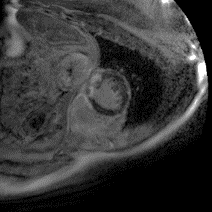

Although supervised deep-learning has achieved promising performance in medical image segmentation, many methods cannot generalize well on unseen data, limiting their real-world applicability. To address this problem, we propose a deep learning-based Bayesian framework, which jointly models image and label statistics, utilizing the domain-irrelevant contour of a medical image for segmentation. Specifically, we first decompose an image into components of contour and basis. Then, we model the expected label as a variable only related to the contour. Finally, we develop a variational Bayesian framework to infer the posterior distributions of these variables, including the contour, the basis, and the label. The framework is implemented with neural networks, thus is referred to as deep Bayesian segmentation. Results on the task of cross-sequence cardiac MRI segmentation show that our method set a new state of the art for model generalizability. Particularly, the BayeSeg model trained with LGE MRI generalized well on T2 images and outperformed other models with great margins, i.e., over 0.47 in terms of average Dice. Our code is available at https://zmiclab.github.io/projects.html.